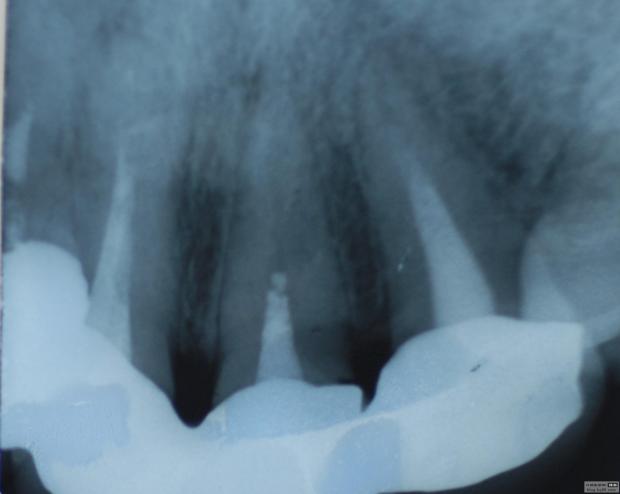

最近接到這樣一位患者,上前牙氧化鋯聯(lián)冠修復(fù)不足一年時(shí)間,現(xiàn)患者主訴左上前牙疼痛來診,檢查發(fā)現(xiàn)上前牙冷熱無反應(yīng),扣診(++),牙齦紅腫,探出血,冠邊緣不密合, X片示基牙全部已做根管治療,但是根管充填全部欠填。

病例1 由于根管充填不完善造成修復(fù)體拆除

修復(fù)后出現(xiàn)根尖周炎癥狀 根管再治療后病變愈合